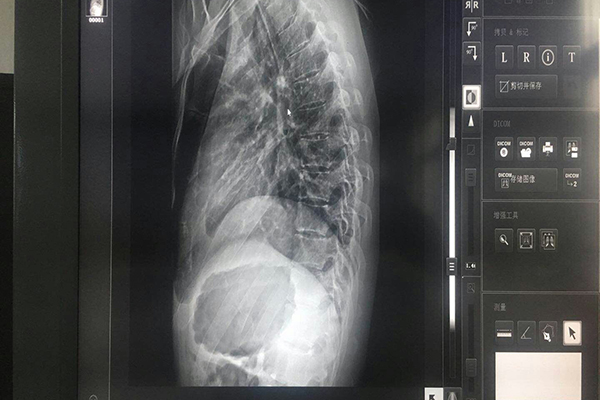

作為現(xiàn)代化手術(shù)室的顯示設(shè)備,內(nèi)窺鏡顯示器能夠真實還原臟器、血管等人體組織,在腫瘤治療中具有非常重要的作用。